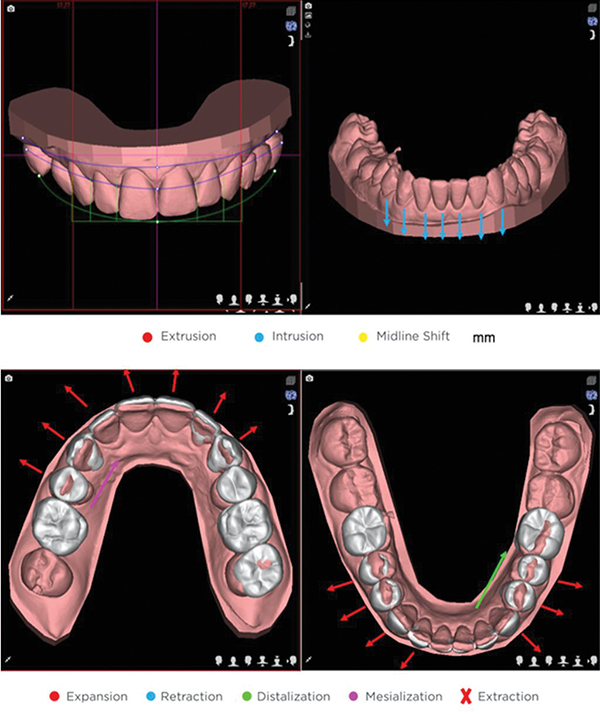

CASE REPORT Facially Driven Interdisciplinary Integrated Digital Orthodontics

Christian Coachman, DDS, CDT; Daniel S.P. Ramos, DDS; Lauren Bohner, DDS, MSc, PhD; Pablo Ramirez-Marrero, DDS; and Newton Sesma, DDS, MSc, PhD

Comprehensive Aligner Therapy for Patients

Marco Pinto, DMD, explains how the ClearPilot 4.0 treatment-planning tool offers flexibility in the customization of treatment options.

FEATURED PRODUCT

Customize with ClearPilot™ 5.0

Powerful editing. Insightful analysis. Comprehensive 3D visual interface. Intuitive software. Check out the updated ClearPilot 5.0 from ClearCorrect.